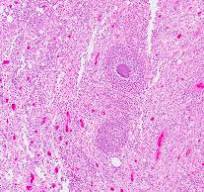

विशेष प्रक्रियाएं: कुछ मामलों में, आगे के विश्लेषण के लिए ऊतक के नमूने प्राप्त करने हेतु बायोप्सी की जा सकती है।

एक्टिनोमाइकोसिस एक दुर्लभ लेकिन महत्वपूर्ण जीवाणु संक्रमण है जो मुख्य रूप से मानव शरीर के नरम ऊतकों को प्रभावित करता है। यह बैक्टीरिया के एक समूह के कारण होता है जिसे एक्टिनोमाइकोसिस के नाम से जाना जाता है। एक्टिनोमाइसेस बैक्टीरिया, जो कि आमतौर पर मुंह और जठरांत्र संबंधी मार्ग में पाए जाते हैं। हालांकि यह एक आम स्थिति नहीं है, लेकिन एक्टिनोमाइकोसिस को समझना अपने आप में काफी महत्वपूर्ण है क्योंकि अगर इसका समय पर उवित उपचार न किया जाए तो यह गंभीर स्वास्थ्य समस्याएं भी पैदा कर सकता है। आज के हमारे प्रस्तुत लेख का उद्देश्य एक्टिनोमाइकोसिस के सम्बन्ध में एक व्यापक अवलोकन प्रदान करना है, जिसमें हमने इसके कारण, लक्षण, निदान, उपचार विकल्प और रोकथाम आदि की रणनीतियों को शामिल किया हैं।

एक्टिनोमाइकोसिस एक संक्रामक रोग है जो जीनस से संबंधित अवायवीय बैक्टीरिया के कारण होता है। एक्टिनोमाइसेस नामक ये बैक्टीरिया मानव शरीर के सामान्य वनस्पतियों का हिस्सा हैं, जो कि खासकर आपके मुंह और आंतों में पाए जाते हैं। हालांकि, कुछ स्थितियों में, वे रोगजनक बन सकते हैं, जिससे फोड़े और ऊतक विनाश के गठन की विशेषता वाले पुराने संक्रमण हो सकते हैं। एक्टिनोमाइकोसिस का सबसे आम रूप सर्विकोफेशियल एक्टिनोमाइकोसिस है, जो आपके चेहरे और गर्दन को प्रभावित करता है, लेकिन संक्रमण वक्ष, पेट और श्रोणि आदि क्षेत्रों में भी हो सकता है।